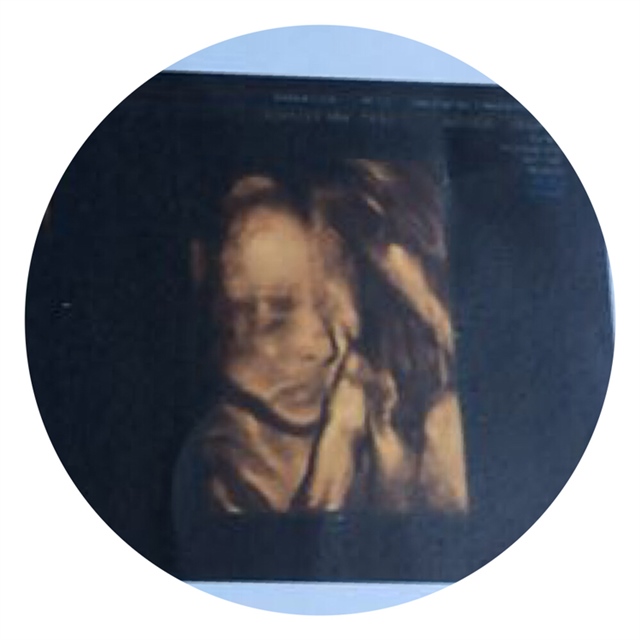

鼻子好漂亮

宝宝看起来是个高鼻梁,挺漂亮的